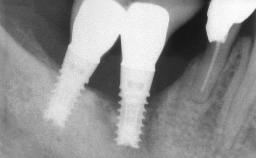

Michael Bornstein

Basel, Switzerland